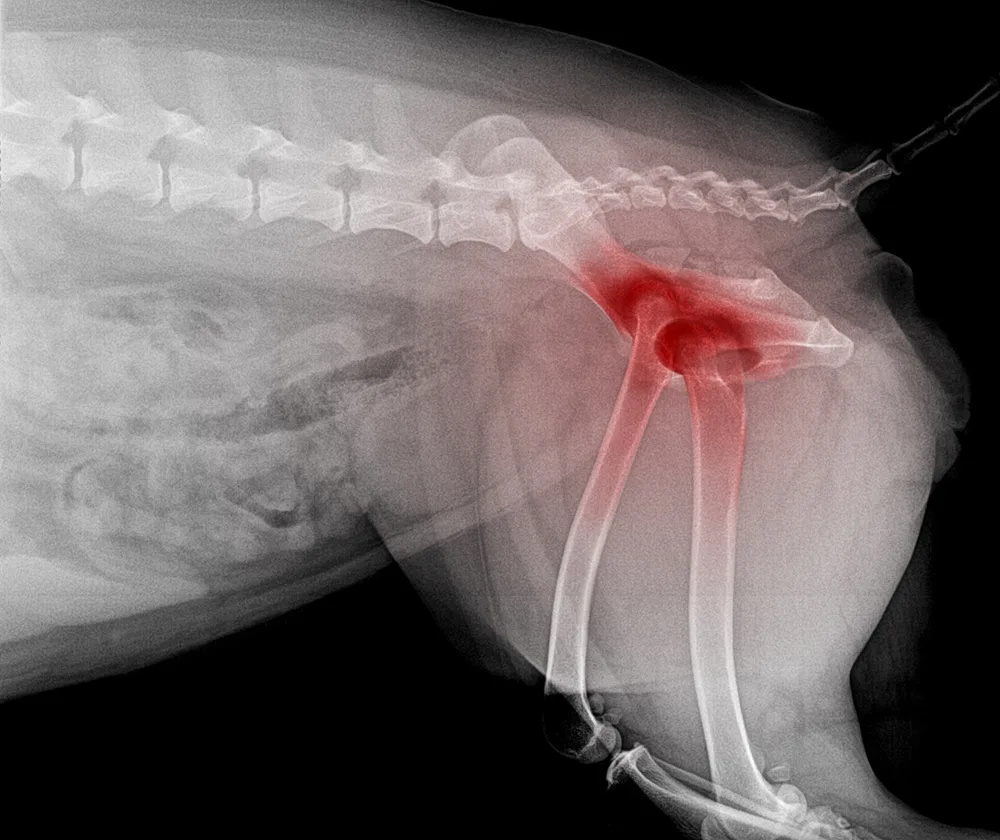

Osteoarthritis (OA) is one of the most common chronic conditions in dogs, and one of the most misunderstood. Many owners attribute stiffness, slowing down or irritability to ‘just getting old,’ when in reality these are signs of pain. Until recently, canine OA treatment options focused mainly on non-steroidal anti-inflammatory drugs (NSAIDs), joint supplements, weight management and physiotherapy.

But the release of Librella® (bedinvetmab) has introduced an entirely new class of pain relief: one that is long-acting, targeted, and specifically designed for chronic arthritis in dogs. If your dog has OA or is showing early signs, this medication may be part of the future of comfort-focused care.

Stiffness after rest, especially when rising from sleep, is one of the earliest and most common signs of canine osteoarthritis, particularly in middle-aged and senior dogs.

SIGNS SUGGESTING ARTHRITIS

• Slow to stand after lying down

• Hesitation on stairs or jumping into cars

• ‘Bunny hopping’ or altered gait

• Less interest in long walks

• Stiffness that improves as they ‘warm up’

• Irritability when touched over hips, back or elbows

• Lyme disease or immune-mediated joint disease

A vet exam and possibly X-rays are the best way to confirm.